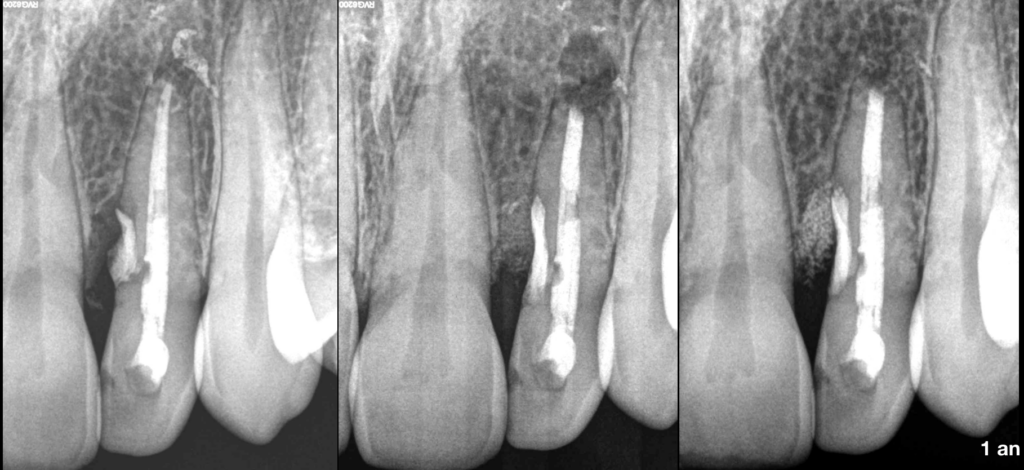

🦷 Indication un peu limite, mais enjeu de taille : 𝐥’𝐢𝐧𝐜𝐢𝐬𝐢𝐯𝐞 𝐥𝐚𝐭𝐞́𝐫𝐚𝐥𝐞 𝐝𝐞 𝐧𝐨𝐭𝐫𝐞 𝐜𝐡𝐞̀𝐫𝐞 𝐩𝐚𝐭𝐢𝐞𝐧𝐭𝐞.

📌 𝐏𝐮𝐥𝐩𝐞 𝐩𝐫𝐞́𝐜𝐞́𝐝𝐞𝐦𝐦𝐞𝐧𝐭 𝐭𝐫𝐚𝐢𝐭𝐞́𝐞

⚠️ 𝐏𝐚𝐫𝐨𝐝𝐨𝐧𝐭𝐢𝐭𝐞 𝐚𝐩𝐢𝐜𝐚𝐥𝐞 𝐬𝐲𝐦𝐩𝐭𝐨𝐦𝐚𝐭𝐢𝐪𝐮𝐞

📍 𝐀𝐓𝐂𝐃 𝐝𝐞 𝐭𝐞𝐧𝐭𝐚𝐭𝐢𝐯𝐞 𝐝𝐞 𝐭𝐫𝐚𝐢𝐭𝐞𝐦𝐞𝐧𝐭 𝐝𝐞 𝐫𝐞́𝐬𝐨𝐫𝐩𝐭𝐢𝐨𝐧 𝐫𝐚𝐝𝐢𝐜𝐮𝐥𝐚𝐢𝐫𝐞 𝐞𝐱𝐭𝐞𝐫𝐧𝐞 : 𝐝𝐞́𝐟𝐚𝐮𝐭 𝐨𝐬𝐬𝐞𝐮𝐱 𝐝𝐞 𝐫𝐞𝐠𝐚𝐫𝐝

🎯 Au programme : 𝐦𝐢𝐜𝐫𝐨𝐜𝐡𝐢𝐫𝐮𝐫𝐠𝐢𝐞

🔹 De la zone 𝐚𝐩𝐢𝐜𝐚𝐥𝐞

🔹 De la zone de la 𝐫𝐞́𝐬𝐨𝐫𝐩𝐭𝐢𝐨𝐧, obturée au CVIMAR + 𝐜𝐨𝐦𝐛𝐥𝐞𝐦𝐞𝐧𝐭 𝐨𝐬𝐬𝐞𝐮𝐱

📅 𝐑𝐞́𝐬𝐮𝐥𝐭𝐚𝐭 𝐞𝐟𝐟𝐢𝐜𝐚𝐜𝐞 𝐚̀ 𝟏 𝐚𝐧, et nous continuerons de surveiller l’efficacité de cette intervention annuellement.